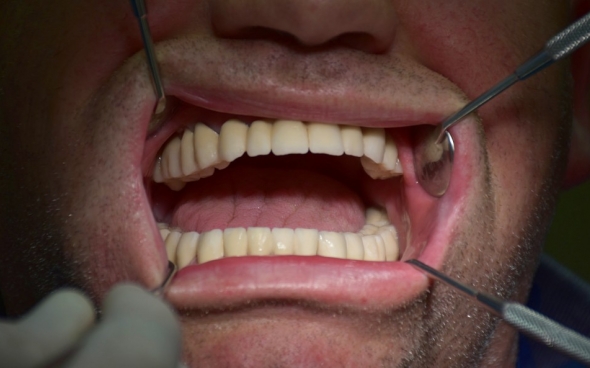

Metallkeramische Oberkiefer- und Unterkiefer-Vollbrücken

Der 48 jährige österreichische Patient erschien an unserer Zahnklinik zu einem Beratungstermin, wo eine Röntgenaufnahme und ein Kostenplan für metallkeramische Vollbrücken im Ober- und Unterkiefer mit insgesamt 25 Kronen erstellt wurden.